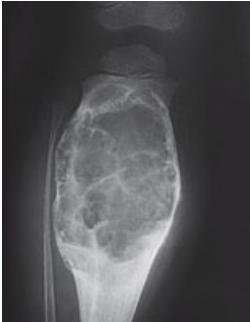

Aneurysmal Bone Cyst

- Child - young adult

- Metaphysis of long bone

- X-ray:

- Well-defined cyst

- Trabeculated

- Eccentrically placed

- Ballooning

- Bloody content

- Treatment:

- Curettage and bone graft

- Metaphysis, Eccentric